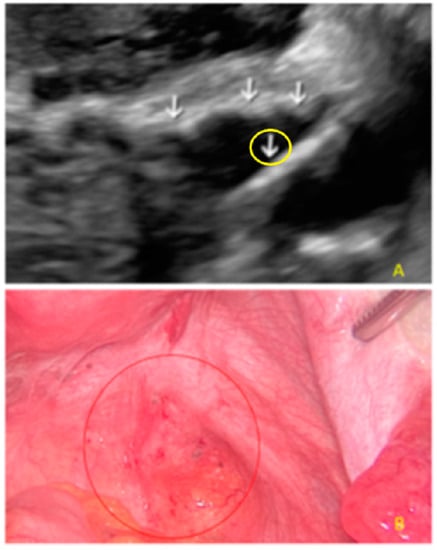

- The lesion may be convex, protruding from the peritoneal surface into the peritoneal cavity (we called this “bulging”), or it may appear as a concave defect in the peritoneum (we called this a “pocket”).

- The presence of hyperechoic foci (we called this a “pearl”).